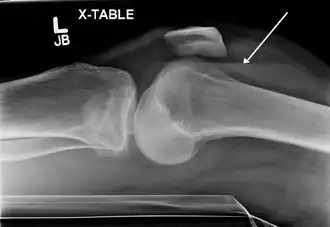

Lipohémarthrose (présence de sang et de graisse dans l'épanchement hémorragique) est une fracture articulaire du plateau tibial interne. La flèche indique un niveau de liquide entre le composant gras supérieur et le composant sanguin inférieur.

L'hémarthrose est un épanchement de sang dans une cavité articulaire consécutif d'une lésion ligamentaire, d'une fracture osseuse ou encore d'une atteinte du cartilage osseux[1]. Cette physiopathologie est caractéristique des personnes atteintes d'hémophilie sévère et dans une moindre mesure chez les formes modérées, car chez les hémophiles, l’absence ou l’altération d’un des facteurs de la coagulation (VIII ou IX selon le type d’hémophilie) perturbe le processus de la coagulation, au point qu’un traumatisme minime peut provoquer un saignement prolongé[2]